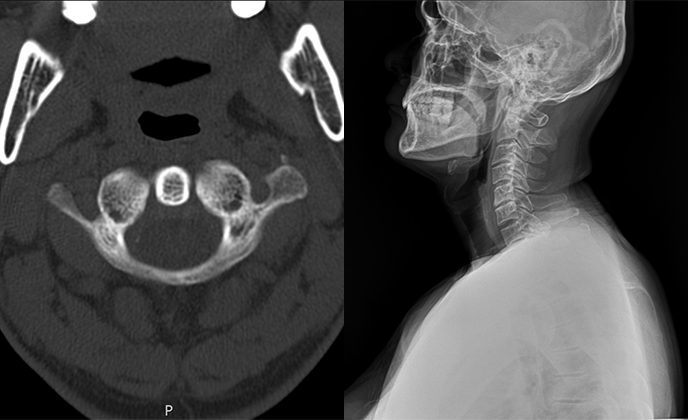

▲ 치료 전 (2016년 1월 21일)

▲ CTA 5개월 착용 (2016년 6월 29일)

▲ CTA 9개월 착용 (2016년 10월 29일)